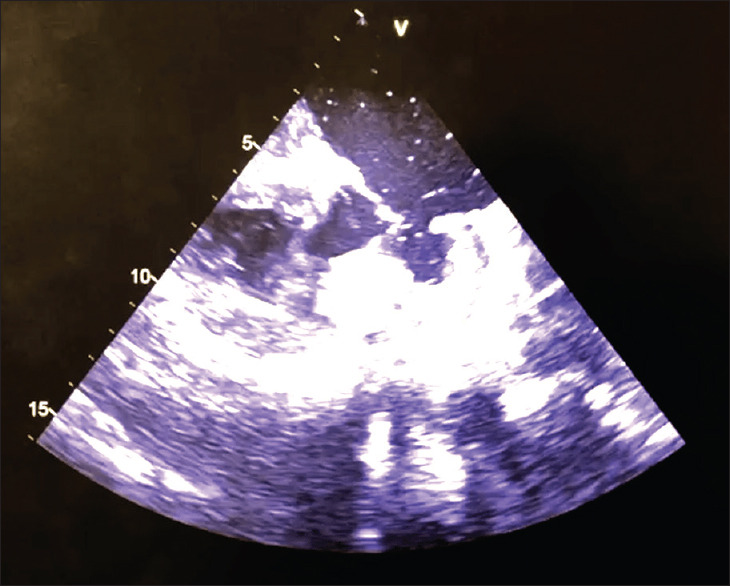

An 11-year-old boy, known case of biventricular restrictive cardiomyopathy was airlifted in a critically ill condition, on multiple inotropes, lapsing in and out of consciousness. He had a history of cardiac arrest. He was oliguric with a brain natriuretic peptide of 23530 pg/ml. Echocardiogram showed bi-atrial enlargement with severe mitral and tricuspid regurgitation and severe pulmonary hypertension [Video 1]. The very short distance of the left ventricular apex from the mitral valve is evident [Figure 1].

Figure 1.

Two-dimensional echo showed biatrial enlargement with left ventricular noncompaction

The surgery was conducted using standard cardiopulmonary bypass. In an empty heart, the apex of the ventricle was found to be very close to the mitral valve [Figure 7].

Figure 7.

Two-dimensional echo image showing the apex of the ventricle was found to be very close to the mitral valve in an empty heart